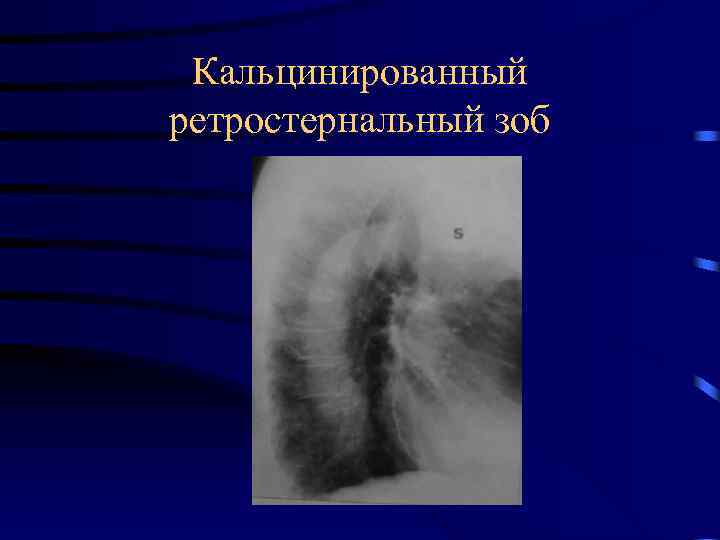

Рентгеновские снимки тератомы средостения: Диагностика и лечение

Раздел: Фотоэссе